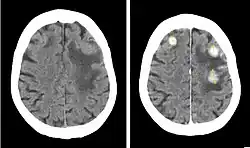

Iopentol (trade name Imagopaque) is a pharmaceutical drug that was used as a radiocontrast agent for X-ray imaging in Europe.[1]

Uses included arteriography (imaging of arteries), venography (imaging of the veins) and CT scan enhancement, urography (imaging of the urinary system), arthrography (imaging of the joints), endoscopic retrograde cholangiopancreatography (ERCP; imaging of bile and pancreatic duct), hysterosalpingography (imaging of the uterus and fallopian tubes), and gastrointestinal studies.[1]

Iopentol is an iodine-containing, water-soluble radiocontrast agent. The iodine atoms readily absorb X-rays, resulting in a higher contrast of X-ray images. It has a low osmolality, meaning that the solution has a relatively low concentration of molecules; this is usually associated with fewer adverse effects than high-osmolality contrast agents.[1][2]